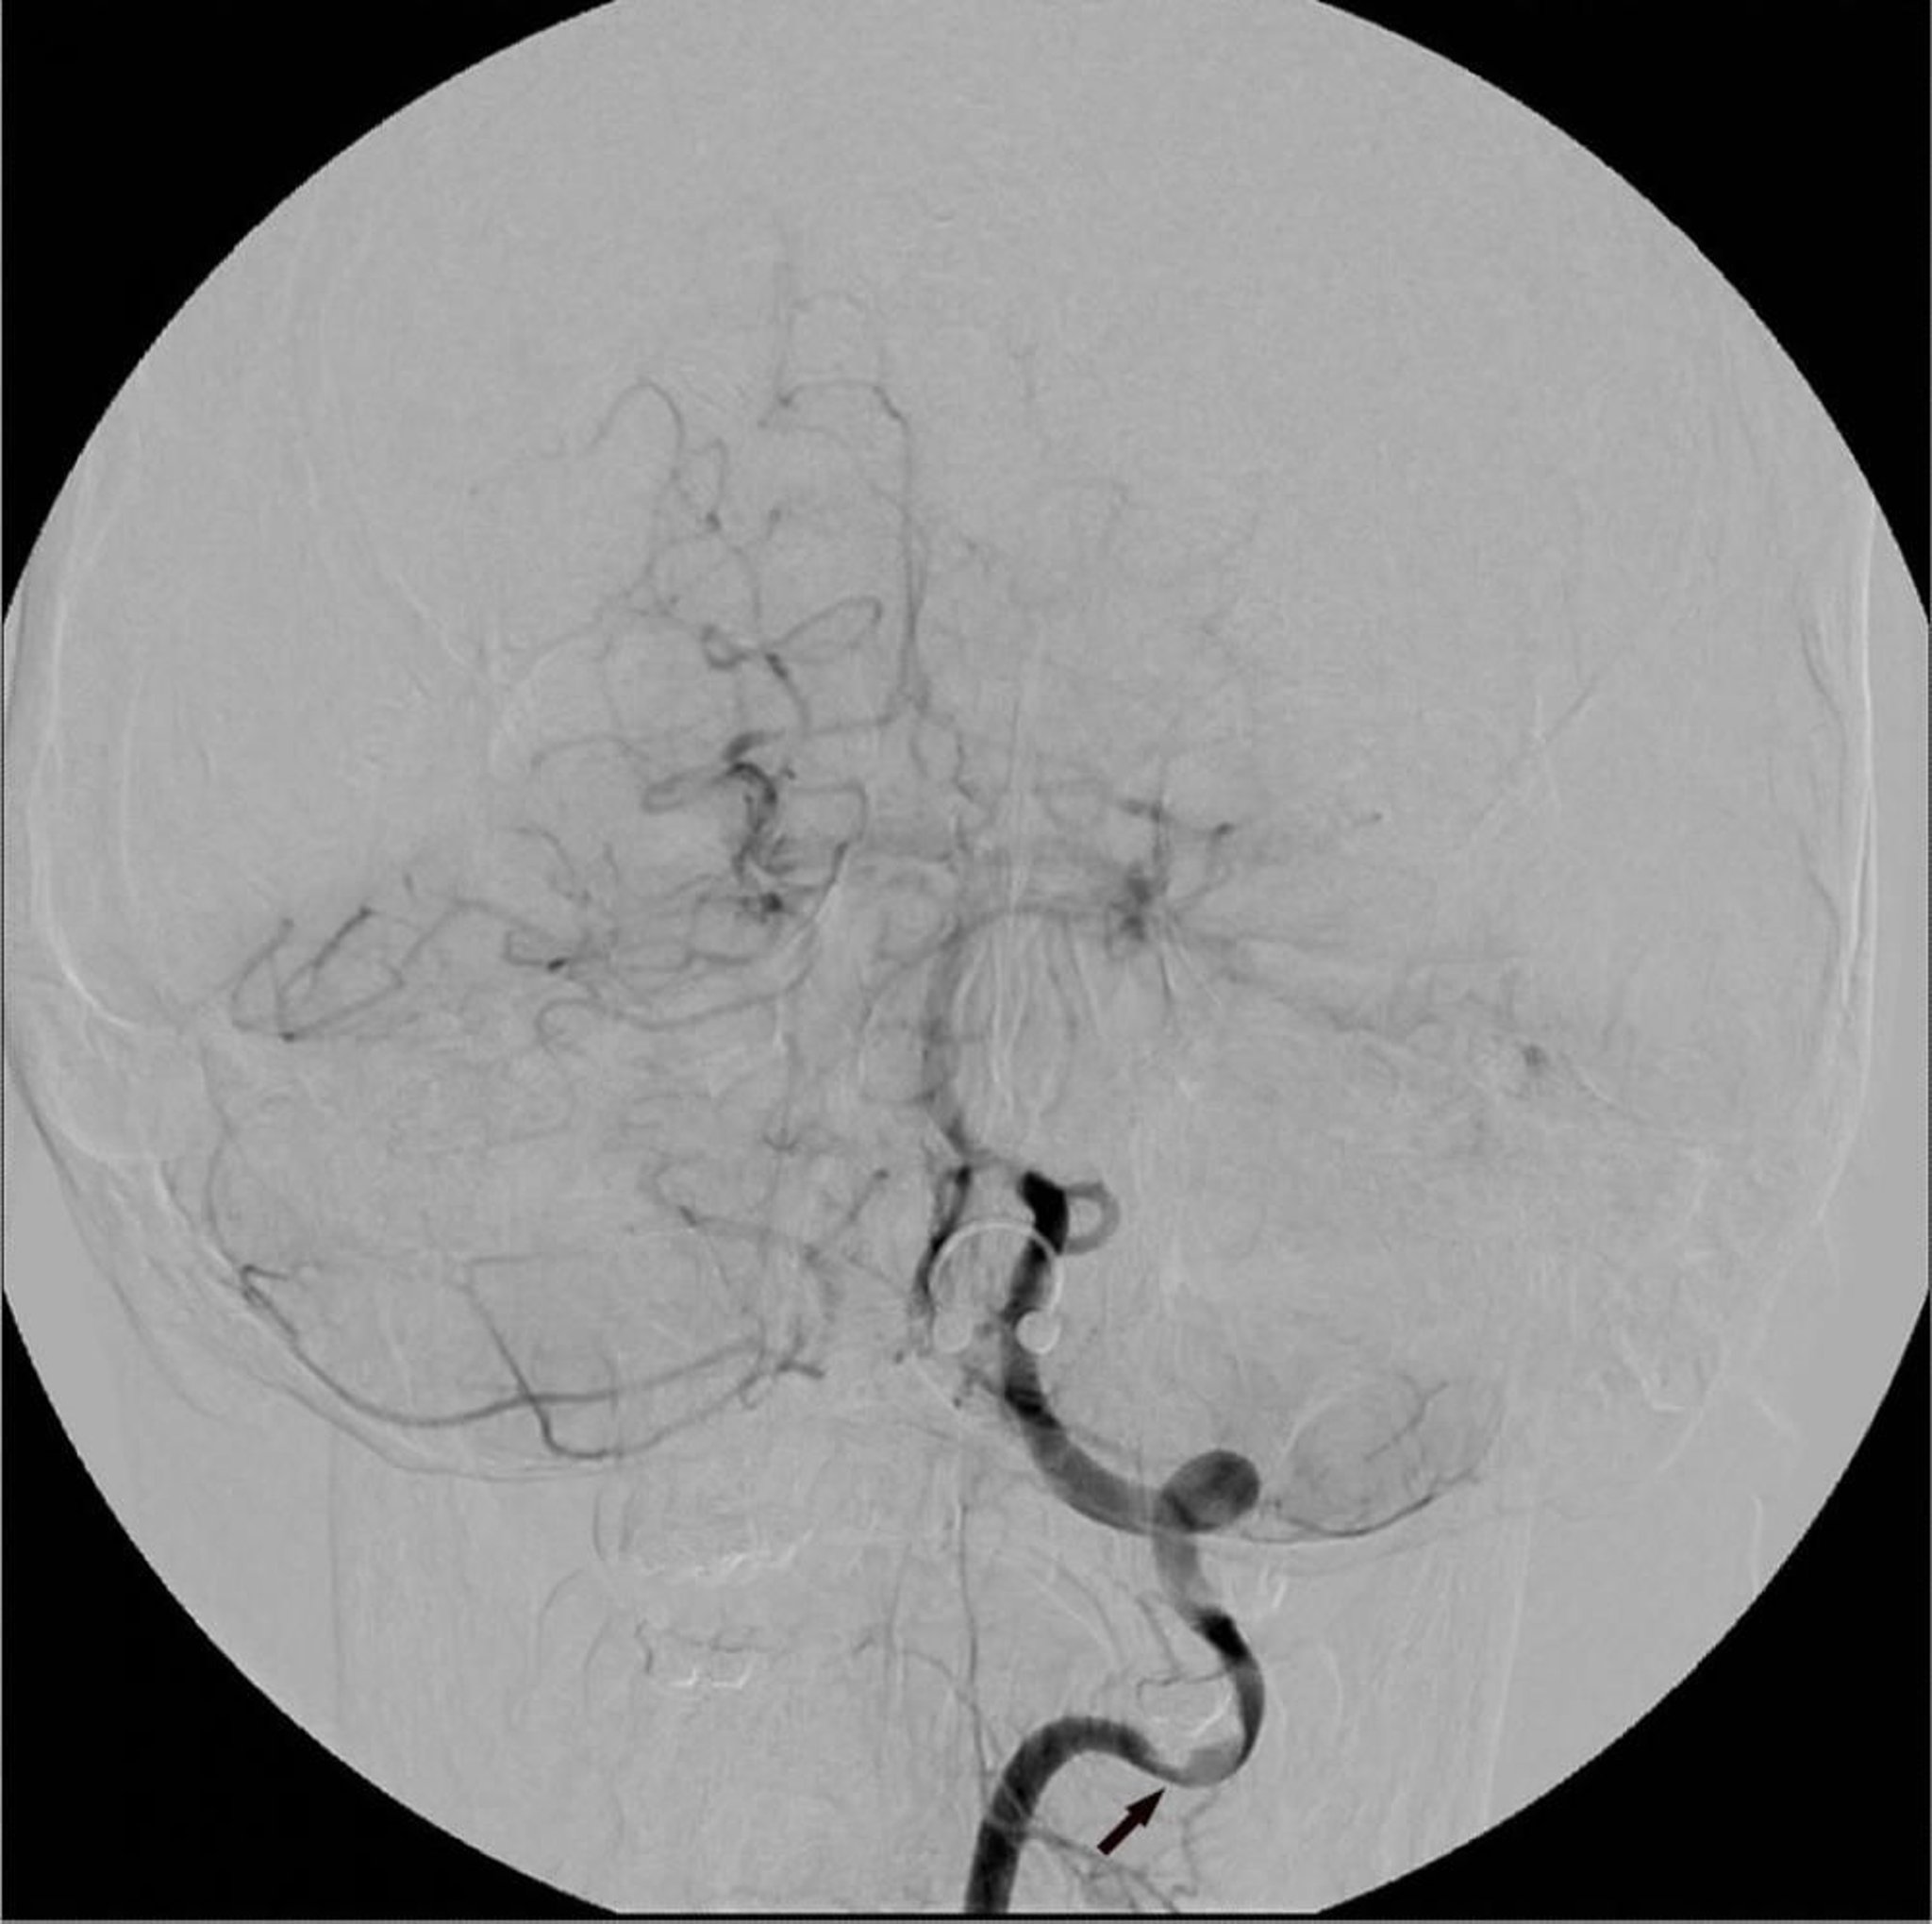

Angiografía por sustracción digital

La angiografía por sustracción digital de la arteria vertebral izquierda muestra un área focalizada de estenosis (flecha).

Image courtesy of Hakan Ilaslan, MD.